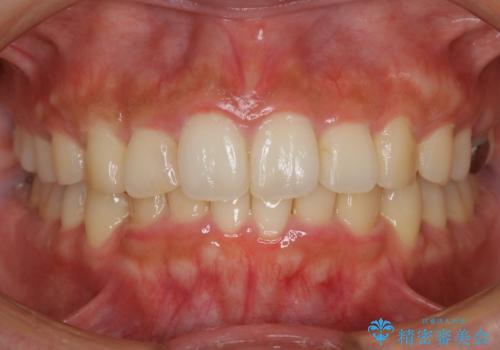

【非抜歯】インビザラインで正しい噛み合わせを

【非抜歯】インビザラインでガタつきと口元を改善!非抜歯でも印象が変わる矯正治療